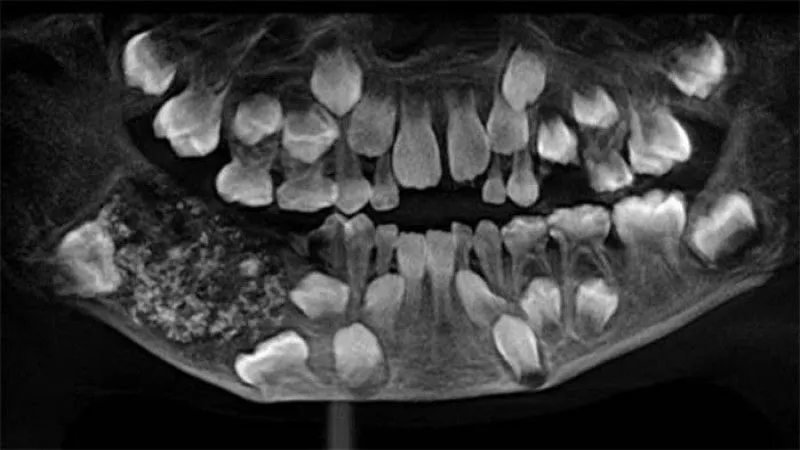

Dr. Prathiba Ramani หัวหน้าแผนกช่องปากและโรคขากรรไกรและใบหน้า เผยว่า ผลการเอกซเรย์กรามและช่องปากของเด็กชายคนนี้ พบว่าที่ขากรรไกรด้านล่างขวาพบบางอย่างคล้ายถุง ภายในเต็มไปด้วยฟันที่ผิดปกติ

หลังจากผ่าตัดนำถุงดังกล่าวออกมาได้ พบว่าภายในเต็มไปด้วยฟัน 526 ซี่ มีตั้งแต่ขนาดเล็ก 01. มิลลิเมตร ไปถึง 15 มิลเมตร บางชิ้นที่เล็กๆ มีครอบฟัน, รากฟัน และเคลือบฟัน ซึ่งหมายความว่ามันคือ ฟันจริงๆ